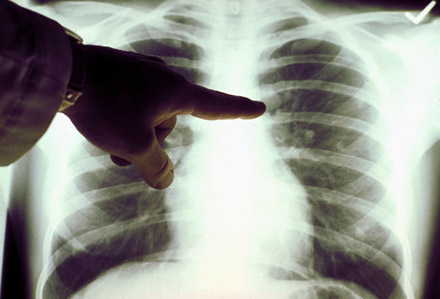

1、X线检查:X线检查是诊断肺癌常用的重要手段。通过X线检查可以了解肺癌的部位和大小。